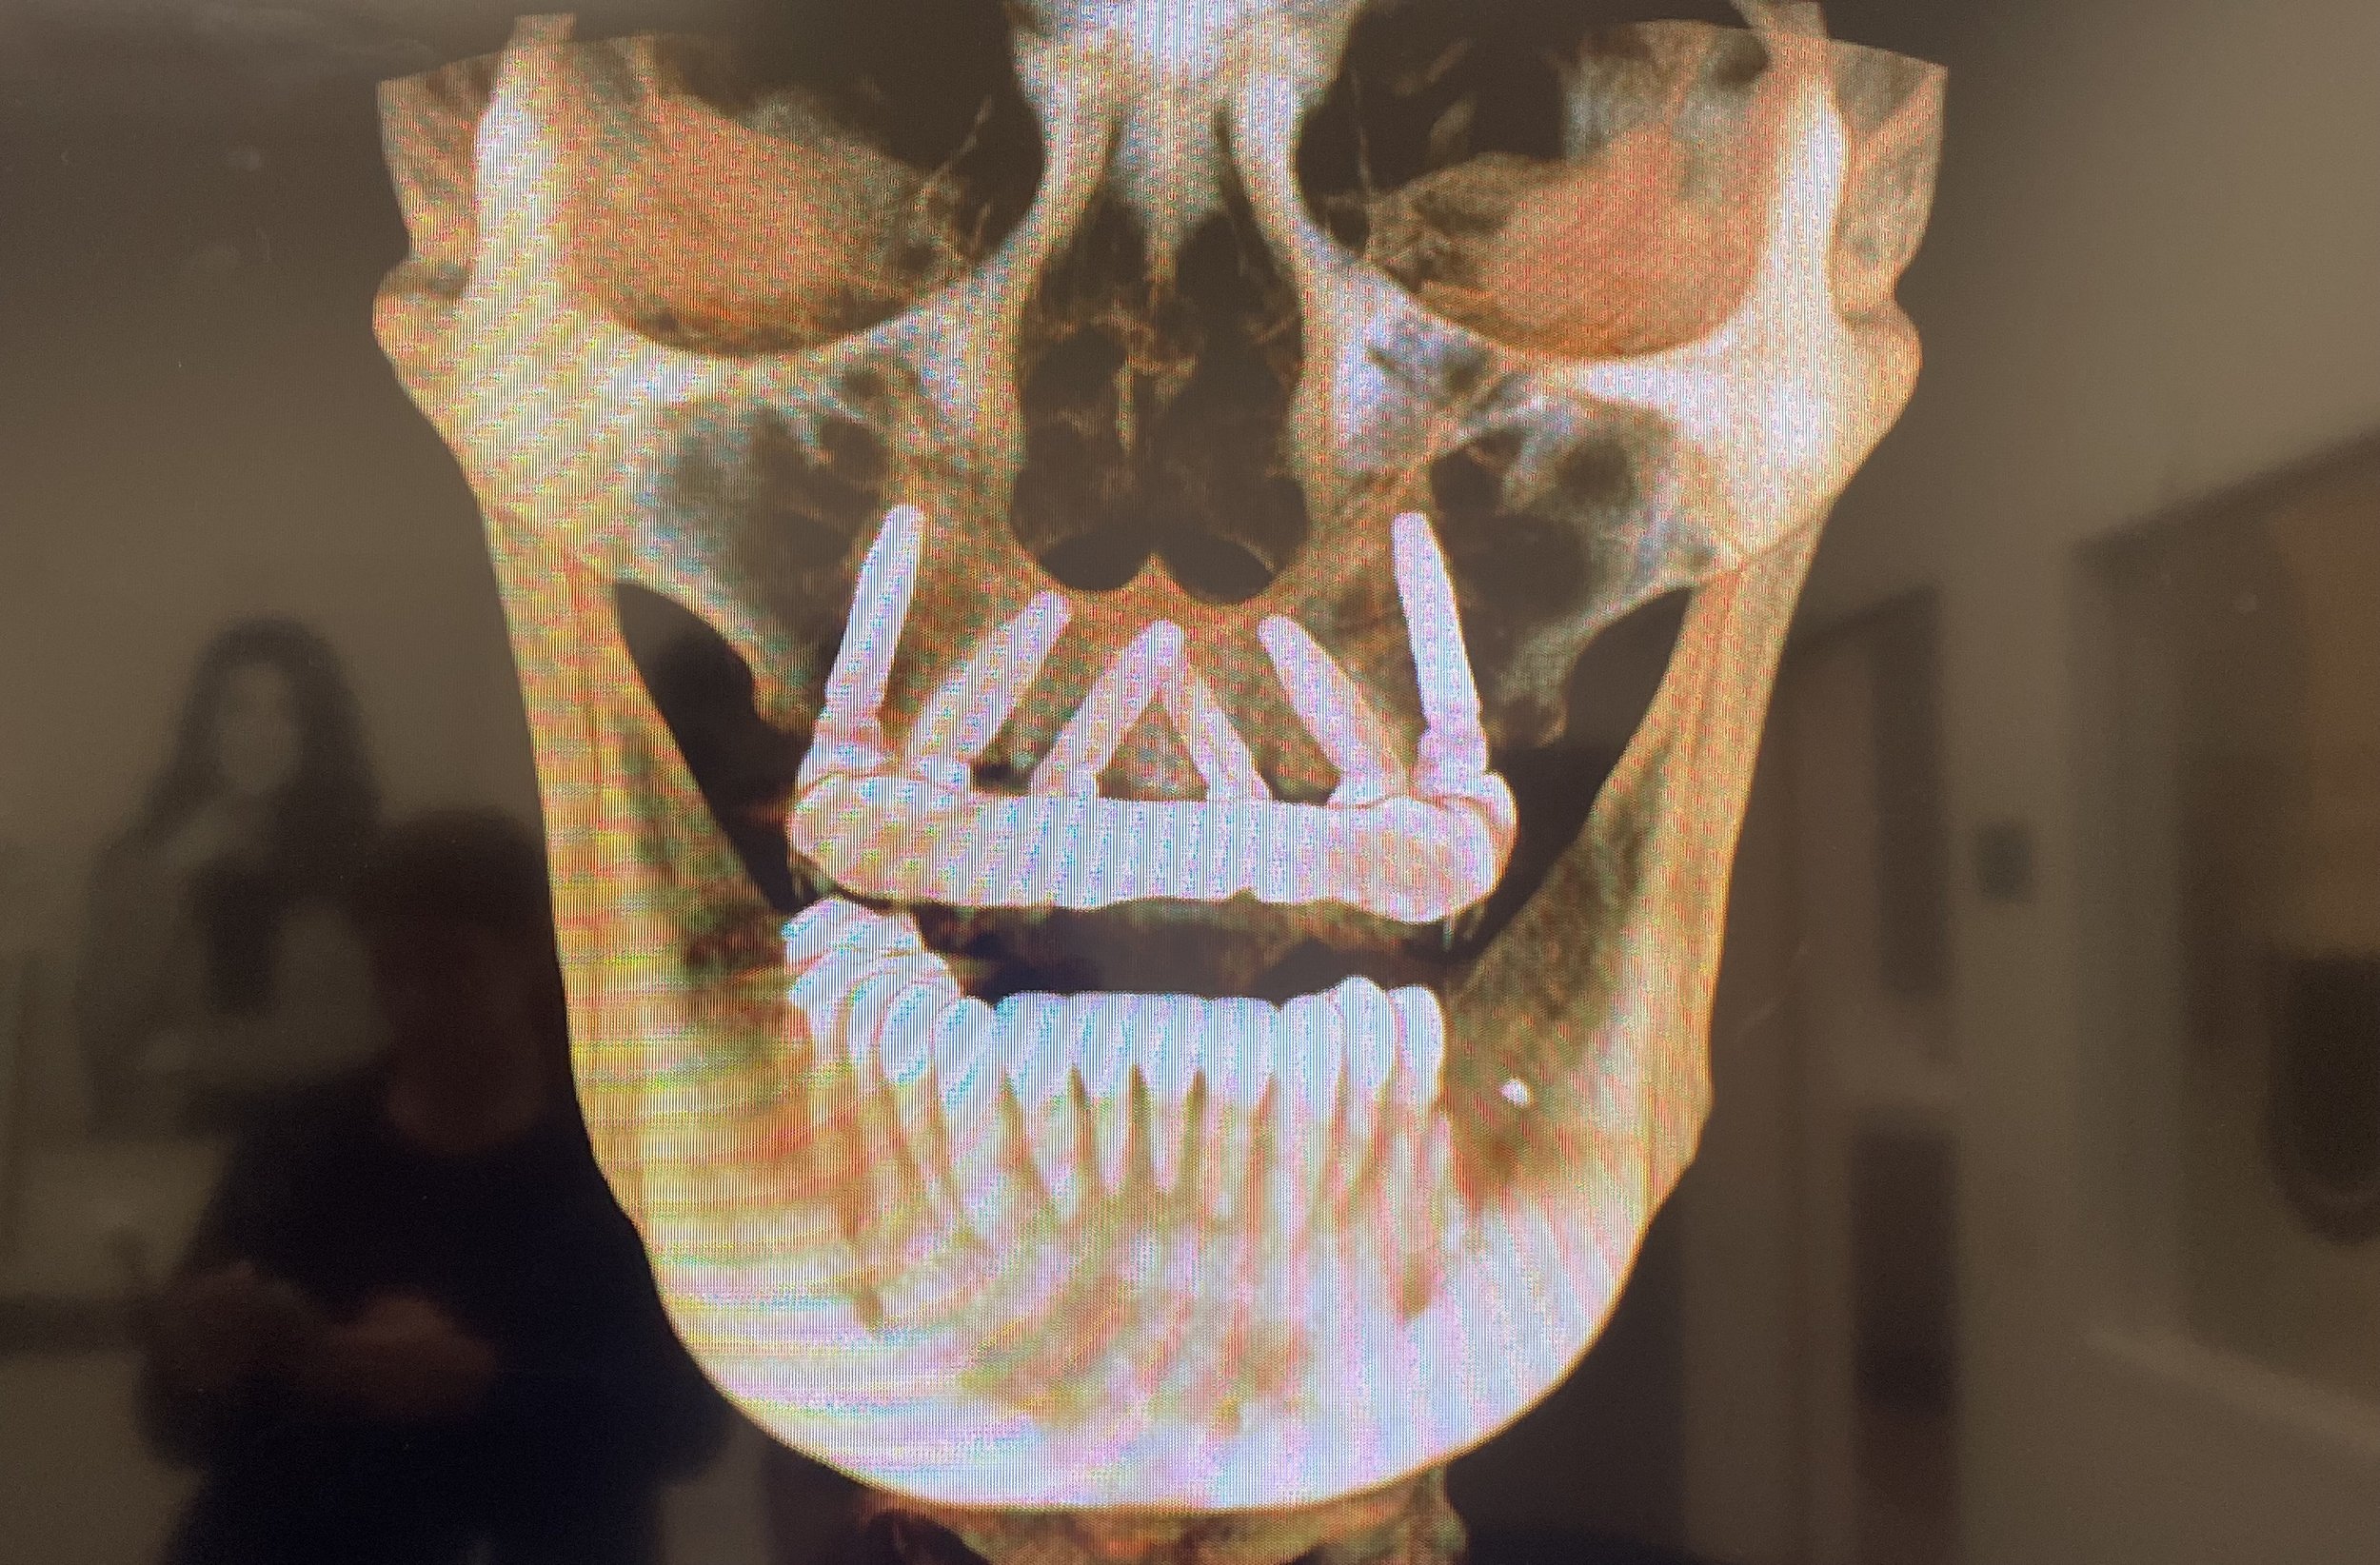

Dr. Damons Cases